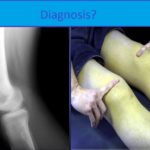

Chronic Osteomyelitis

Courtesy: Saqib Rehman MD Associate Professor Director of Orthopaedic Trauma Temple University Philadelphia, Pennsylvania USA www.orthoclips.com CHRONIC Osteomyelitis The term ‘osteomyelitis’ originates from the two Greek words ‘osteon’ and ‘myelos’ – bone and marrow The French surgeon Edouard Chassaignac was the first to introduce the term osteomyelitis in 1852 INTRODUCTION Chronic osteomyelitis is defined […]